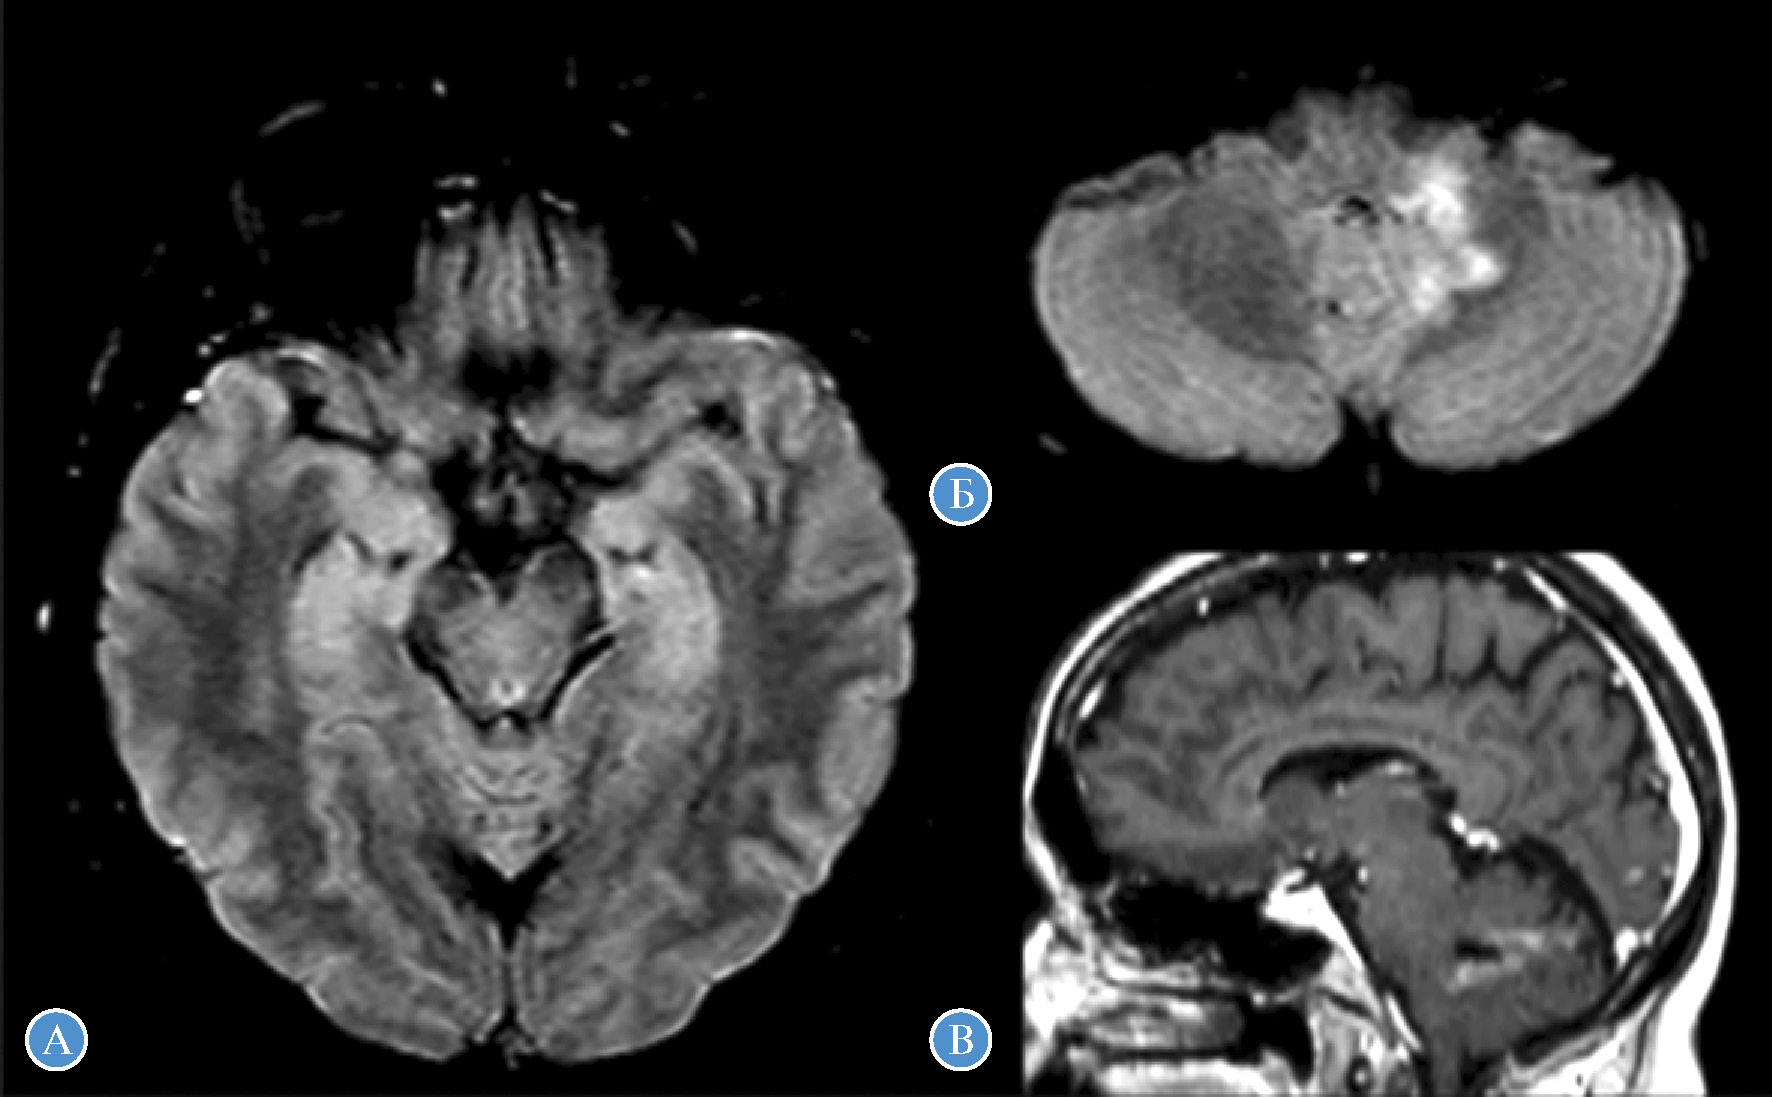

При МРТ головного мозга у 42% изменений обнаружено не было. У 6 (50%) пациентов выявлены признаки атрофии мозжечка от легкой до умеренной степени: атрофия червя мозжечка (n = 3), диффузная атрофия мозжечка (n = 2), гемиатрофия полушария мозжечка (n = 1) (рис. 2). В одном случае (пациентка #19) наблюдались Т2/T2-FLAIR-гиперинтенсивные изменения от медиальных отделов височных долей и структур мозжечка с признаками патологического накопления контрастного вещества на постконтрастных Т1 (Т1-С+) взвешенных изображениях (рис. 3). Примечательно, что, несмотря на МРТ-данные о вовлечении височных долей, клиническая картина заболевания была представлена МА и лишь легким когнитивным дефицитом (MoCA — 24 балла). С учетом нетипичной МРТ-картины пациентке проводился обширный онкологический поиск — патологии не обнаружено.

Рис. 3. МРТ головного мозга пациентки #19: А, Б — Т2-FLAIR, аксиальные срезы; В — Т1-С+, сагитальный срез. Гиперинтенсивность от медиобазальных отделов височных долей (А), гиперинтенсивная зона неправильной формы в медиальных отделах левого полушария мозжечка с распространением на среднюю мозжечковую ножку, левые отделы червя (Б) с неоднородным патологическим накоплением контрастного вещества (В)

МРТ головного мозга может обнаруживать изменения у пациентов с МА и ЛЭ/Э. Порядка половины случаев GAD-МА имеют МР-признаки атрофии мозжечка (наиболее часто — червя). Подобно другим иммуноопосредованным МА, церебеллярная атрофия нередко отсутствует в начале заболевания, но развивается с течением времени [15, 16, 25]. Примерно у 40% GAD-ЛЭ/Э выявляются двусторонние Т2-гиперинтенсивные изменения от медиальных отделов височных долей и гиппокампов, без патологического накопления контрастного вещества [11]. Признаки височной кортикальной атрофии, как правило, отсутствуют в дебюте GAD-ЛЭ/Э, но зачастую присоединяются спустя 6–12 мес [27]. МРТ-данные наших пациентов соответствовали описанным ранее. Однако одно наблюдение МА (пациентка #19) было нетипичным, обнаружив воспалительные изменения от височных долей и в левом полушарии мозжечка с неоднородным накоплением контрастного вещества (см. рис. 3). При МРТ в динамике (через 4 мес после инициирования терапии ритуксимабом) патологического накопления контрастного вещества не отмечалось, интенсивность и размер Т2-гиперинтенсивных зон несколько уменьшились. В литературе мы не встретили описаний GAD-МА с подобной МРТ-картиной.